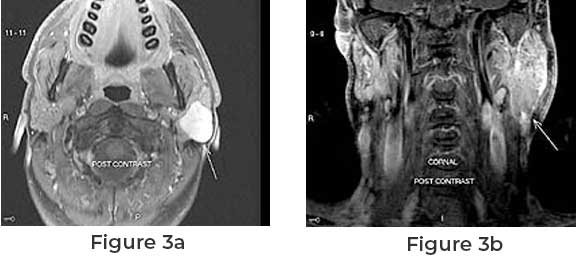

A thorough examination by a healthcare professional may reveal the presence of a lump or swelling. Imaging tests such as ultrasound, MRI, or CT scans can provide detailed images of the tumor and its surrounding structures.